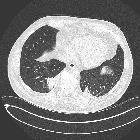

Round

atelectasis in sarcoidosis. CT image at the level of the right lower lobe bronchus shows an oval mass abutting the pleura, pulmonary vessels curving toward the opacity with parenchymal nodules.